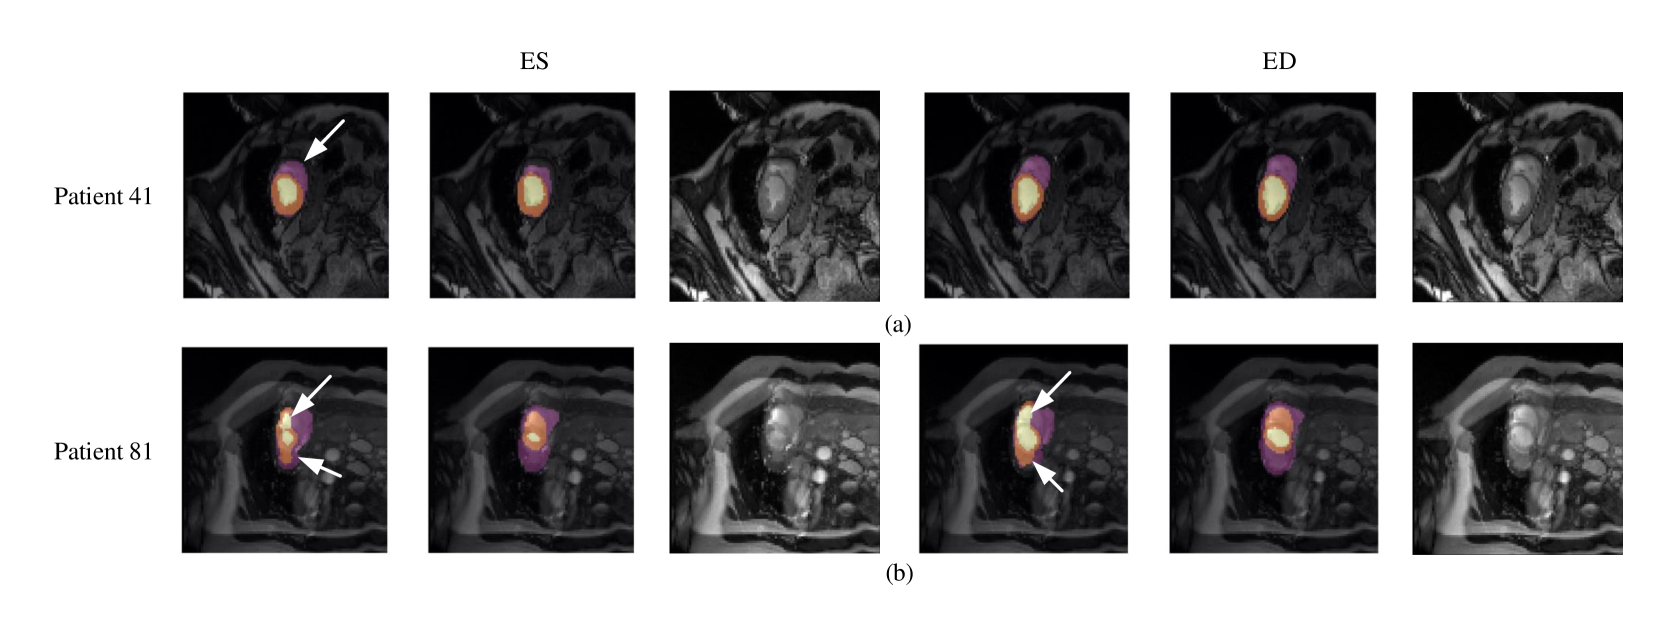

Refer to caption

Figure 9: Typical segmentation error of our framework. The figure shows segmentation result for patient 41 and 81 in both ES and ED phases. The image on Column 1 and 4 are the segmentation results, and images on Column 2 and 5 are the corresponding ground truth. The segmentation error is usually caused by brightness heterogeneity, lack of contrast, or the improper input image due to faulty setup of magnetic resonance system or the misoperations of operators.

Quantitative segmentation results and grading results demonstrate the superiority of our framework compared with the Res U-net baseline implementation. However, there are still some cases where our framework cannot predict reasonable boundaries. For example, Figure 9 (a) shows the segmentation results of Patient 41 in ES and ED phases by our framework. We can notice that there exists deviation between the ground truth boundary (images on Column 2 and 4) and the prediction boundary (images on Column 1 and 3). This is because the flow of blood in RV cavity leads to the brightness heterogeneity in the RV area of CMR image, which makes the image intensity of the ground truth RV region similar to the surrounding cardiac structures (e.g., heart chambers), and finally leads to segmentation failure.

There are some cases as shown in Figure 9 (b) in which CMR sequence have serious defect and ghosting. This may be caused by the improper setup of the magnetic resonance system or the mistake of operators. Therefore, it is hard for our framework to find a plausible myocardial boundary even though our framework is able to correct some segmentation error based on temporal information between frames.